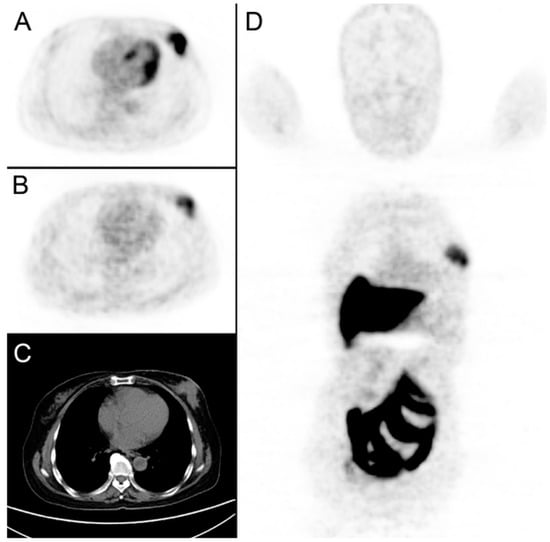

Figure 6.

An example of a breast cancer patient receiving both [18F]FDG and [18F]FES-PET/CT scans prior to neoadjuvant chemotherapy. (A): A tumor was detected in left breast with [18F]FDG SUVmax at 13.51. (B,D): [18F]FES SUVmax at 4.3. (C): CT imaging with the tumor diameter measured at 5.3 cm.

While the predominant usage of [18F]FES PET was to evaluate metastatic breast cancer with salvage endocrine therapy, there is a small number of studies using [18F]FES PET to image the primary breast tumor in the neoadjuvant therapy paradigm [,] (Figure 6). In a small 18-patient cohort receiving NAC, baseline [18F]FES and [18F]FDG uptake was correlated to histopathologic response [,]. This study suggested [18F]FES and [18F]FDG provided similar information in ER+ patients receiving NAC. In another recent study, [18F]FES PET was used to evaluate neoadjuvant treatment response in post-menopausal ER+ breast cancer patients randomized to the NAC vs. the NET arm of the NEOCENT trial (N = 26) []. An important finding from this study was that patients who were [18F]FES-negative or -low (SUV cutoff < 7.3) at baseline achieve a higher rate of pCR in the NAC arm compared to [18F]FES-avid patients. None of the [18F]FES-negative and -low patients responded to NET. While all the patients in this study were ER+, some patients were [18F]FES-negative, indicating the existence of non-functional ER that may be resistant to endocrine treatment. Adequately powered prospective studies in a larger number of ER+ patients are needed to further establish the role of [18F]FES-PET in evaluating response to NET [].